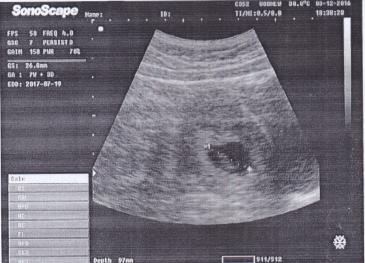

This is my first pregnancy and I am very much exited to know my baby's gender. This is my 7 week ultrasound abdominal scan report. I would be so grateful if you could see my scan report and tell if its boy or girl baby.

Attachment 33973

Pasteboard — Uploaded Image